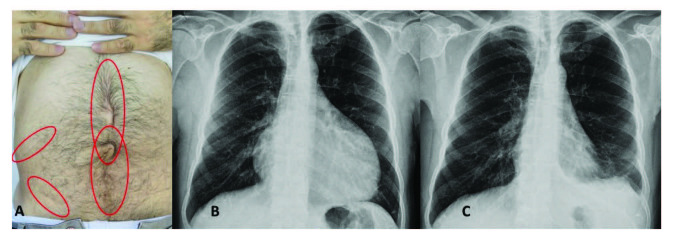

腹膜發(fā)作開始局限并迅速蔓延至整個(gè)腹部。腹膜炎癥會(huì)導(dǎo)致典型的腸梗阻癥狀,患者會(huì)遭受嚴(yán)重的胃痛。體格檢查顯示腹部肌肉僵硬、反跳痛和腸鳴音消失——臨床上這種緊急情況與急腹癥的手術(shù)原因無法區(qū)分。因此,隱匿性腹部手術(shù)史在良性陣發(fā)性腹膜炎患者中很常見(圖 1A)。在疑似病例中,影像學(xué)檢查可能有助于排除手術(shù)病理。腹部發(fā)作后可能會(huì)出現(xiàn)輕度反彈性腹瀉。盡管有戲劇性的表現(xiàn),但腹膜炎的所有體征和癥狀在 24-72 小時(shí)內(nèi)有效消退,沒有后遺癥,盡管慢性腹水和腹膜粘連的報(bào)道很少。

包含圖片、插圖等的外部文件。對象名稱為 turkjmedsci-50-1591-fig001.jpg

圖1:(A) 一位因多次腹部手術(shù)而留下疤痕的患者,(B) 胸部 X 光片顯示大量心包積液,(C) 同一患者用阿那白滯素治療后的胸部 X 光片。

心包炎是一種罕見病癥,見于 1%–2% 的患者。心包炎會(huì)出現(xiàn)胸骨后胸痛和呼吸困難等癥狀。心包填塞可能很少發(fā)生。心電圖顯示 ST 段抬高,胸部 X 光片可能顯示心臟輪廓的短暫擴(kuò)大(圖 1B 和 1C),超聲心動(dòng)圖顯示心包積液。在極少數(shù)情況下,反復(fù)性心包炎可能是良性陣發(fā)性腹膜炎的少有表現(xiàn),這可能與特發(fā)性心包炎相混淆 。